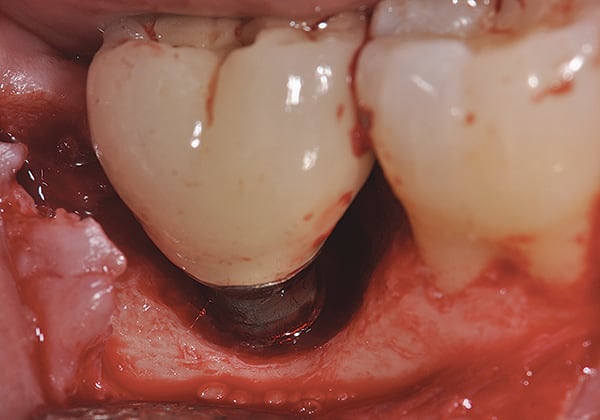

Given what is known about the etiology of peri-implant mucositis and peri-implantitis and the importance of rendering treatment at the earliest possible stage, there are steps that clinicians should take to prevent and minimize the negative sequelae of these biologic complications. Peri-implant diseases present in two forms: peri-implant mucositis (Figure 1 and Figure 2) and peri-implantitis (Figure 3 and Figure 4). Both involve an inflammatory reaction in the tissues surrounding an implant—ie, BOP and/or suppuration and probing depths usually exceeding 4 mm.1,2 However, when there is also bone loss present beyond the physiologic remodeling that may occur after implant placement, a diagnosis of peri-implantitis should be made because this condition, when compared to mucositis, is far more serious and difficult to resolve.3

Treatments aimed at controlling inflammation and infection and limiting biologic complications for peri-implant mucositis and peri-implantitis, respectively, are identical to those that have been found to be effective for gingivitis and periodontitis, respectively. Similar to gingivitis, when detected early peri-implant mucositis can be successfully treated with effective nonsurgical efforts aimed at elimination of the biofilm from the implant surface21,23,24 (Figure 5 through Figure 7), such as supportive periodontal therapy and mechanical nonsurgical treatment.

However, these methods have been reported to be far less effective once the condition has progressed to peri-implantitis. Moreover, flap-access surgical approaches with or without targeted antimicrobial treatment has been met with limited success.25,26 In the authors’ opinion, surface decontamination must completely eradicate the biofilm, debris, and excess cement. Recently, evidence has suggested that a dual antibiotic approach may be more appropriate rather than a single medication.27

The authors, both of whom are periodontists, believe that dentists should make every effort to save a failing tooth before replacing it with an implant because implants are not immune to complications and do not integrate 100% of the time. Moreover, the authors consider efforts to save implants far preferable to extraction and replacement with another implant given the time and the cost for such treatment. They, along with their colleagues, have successfully achieved improvement in bone loss for both teeth28 and implants with a regenerative approach that emphasizes surface decontamination. Dental implants, with their roughened surface topography that is designed to enhance osseointegration, require that this comprehensive regenerative approach employ these tactics: aggressive surface decontamination with mechanical and chemotherapeutic approaches; the administration of systemic antibiotics; regenerative therapy with bone and bone replacement grafting; and the use of biologics and barrier membranes, all followed by a tightly controlled maintenance approach (Figure 8 through Figure 11). In fact, in one case series article this approach to care has demonstrated promising results for up to 8.5 years postsurgery.29,30 This therapy is quite complex and significant experience is essential if success is to be consistently achieved.